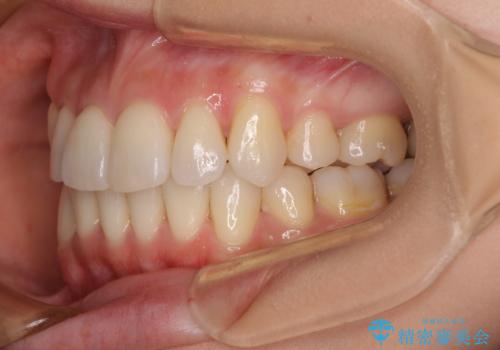

- デコボコの歯列で歯磨きがしにくいことを気にして来院された患者様です。

上下左右の第一小臼歯4本を抜歯して行うことになりますが、それだけでは咬み合わせの改善や正中位置の改善が困難であると判断されたため、アンカースクリューを用いた補助装置を併用することで、スムーズかつより良い仕上がりを目指すこととしました。

途中むし歯が見つかり、矯正治療を行いながら迅速に対応し、何とか神経組織を保存して治療を終えることができました。